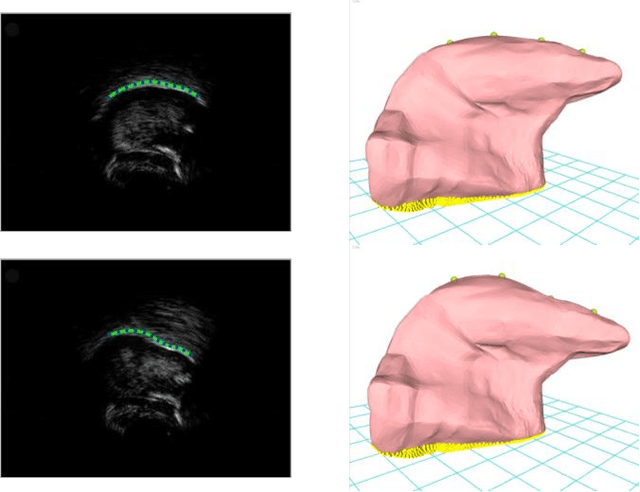

Abstract:This article describes the development of a platform designed to visualize the 3D motion of the tongue using ultrasound image sequences. An overview of the system design is given and promising results are presented. Compared to the analysis of motion in 2D image sequences, such a system can provide additional visual information and a quantitative description of the tongue 3D motion. The platform can be useful in a variety of fields, such as speech production, articulation training, etc.

Abstract:This article describes a contour-based 3D tongue deformation visualization framework using B-mode ultrasound image sequences. A robust, automatic tracking algorithm characterizes tongue motion via a contour, which is then used to drive a generic 3D Finite Element Model (FEM). A novel contour-based 3D dynamic modeling method is presented. Modal reduction and modal warping techniques are applied to model the deformation of the tongue physically and efficiently. This work can be helpful in a variety of fields, such as speech production, silent speech recognition, articulation training, speech disorder study, etc.